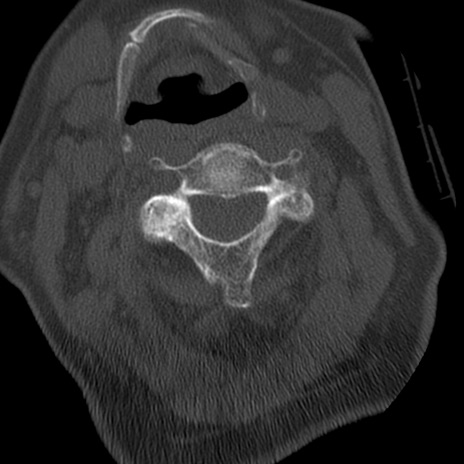

症例50 頚椎CT(横断像)

冠状断像